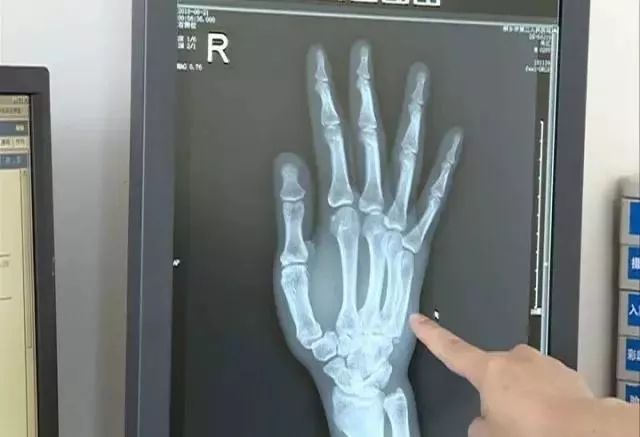

看世界杯把手拍斷:6月20日晚,浙江省桐鄉市崇福鎮小伙28歲的小沈在家看烏拉圭對陣沙特的比賽,看到自己支持的烏拉圭球隊處于劣勢,小沈使勁拍桌子,結果把手拍骨折了。

小沈的手掌骨折,并且骨折處骨頭還有些移位,于是醫生立即為他進行了治療。

醫生表示,小沈的手需要4到6周時間才能恢復。另外,像小沈這樣因為看球而進醫院的例子其實也并不少見,醫生提醒,看球還是應該理性一點。